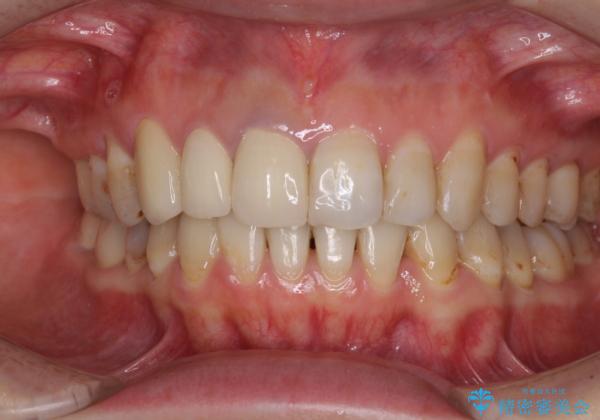

- 前歯の歯並びやむし歯治療の跡、奥歯の銀歯を気にして来院された患者様です。

インビザラインによる矯正治療の後に虫歯や銀歯をセラミックにて補綴することとしました。

前歯のむし歯治療の跡や奥歯の目立つ銀歯がなくなり、明るい口元になりました。